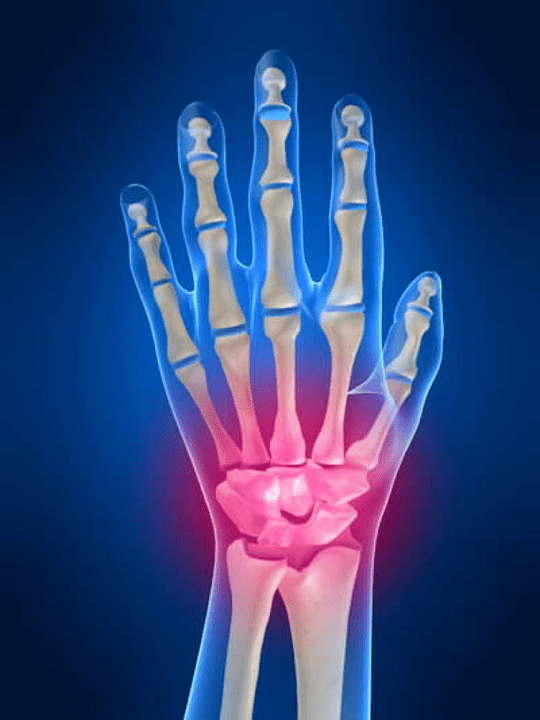

Анатомия на ставите на ръката

Всички стави на ръката са обичайни да бъдат разделени на следните групи:

- китка за китка;

- стави на китката;

- карпални-шарнирни стави;

- междуучиални стави;

- Парлемонално-Фаланкс стави;

- Интерфаланкс стави.

Китката

Съединената става се образува от костите на проксималните кости (горна част) Редица китки (триедрични, полумоуни, скафоидни кости) и дистални области на радиационни и лакътни кости. Костта на лакътя не е пряко свързана с костите на китката, а с помощта на дистални (По -ниско) Артикуларният диск. Тази структура отделя кухината на китката на ставата от дисталната кухина (По -ниско) Свойската фуга.